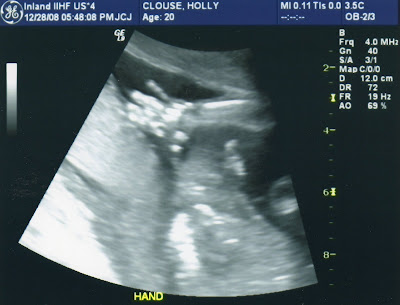

It's a....

Girl!!

We were supposed to find out Chrismas Eve, but due to Nathan having to work and snowstorms, the big ultrasound was postponed till last night. I had talked myself into having another boy (I was excited for Landon to have a little brother) that I am still slightly in shock that we are having a baby girl...but very, very excited! She looks very healthy and is right on time for the due date of May 24th, though I am hoping she is a little early like her brother. She doesn't move nearly as much as Landon did, but when she does she kicks very hard. She enjoyed head butting me the whole time the tech did the ultrasound, and almost didn't let us know what she was. :) We are very happy, thrilled with how healthy she seems right now, and grateful to God for another incredible blessing. What joy!